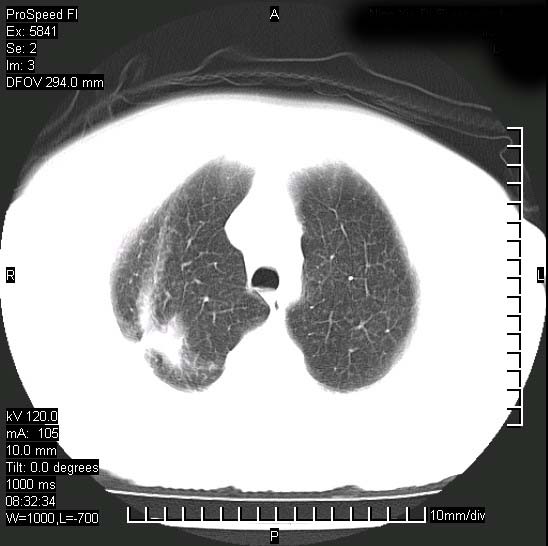

胸痛,咳嗽,气短一周,无发热。右上肺见一结节灶,边缘刺角,内见多个小钙化结节。考虑结核球?肿瘤? 余无异常没有上传。

考虑右肺上叶继发性肺结核,结核球形成。

胸膜是受侵的,考虑感染,结核球可能性大

考虑结核球,并胸膜局限性增厚!!